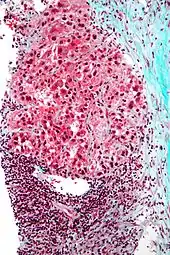

| Hepatocellular carcinoma in an individual who was hepatitis C positive. Autopsy specimen. | |

Pathology

Macroscopically, liver cancer appears as a nodular or infiltrative tumor. The nodular type may be solitary (large mass) or multiple (when developed as a complication of cirrhosis). Tumor nodules are round to oval, gray or green (if the tumor produces bile), well circumscribed but not encapsulated. The diffuse type is poorly circumscribed and infiltrates the portal veins, or the hepatic veins (rarely).[16]

Microscopically, the four architectural and cytological types (patterns) of hepatocellular carcinoma are: fibrolamellar, pseudoglandular (adenoid), pleomorphic (giant cell), and clear cell. In well-differentiated forms, tumor cells resemble hepatocytes, form trabeculae, cords, and nests, and may contain bile pigment in the cytoplasm. In poorly differentiated forms, malignant epithelial cells are discohesive, pleomorphic, anaplastic, and giant. The tumor has a scant stroma and central necrosis because of the poor vascularization.[39] A fifth form – lymphoepithelioma like hepatocellular carcinoma – has also been described.[40][41]

Micrograph of hepatocellular carcinoma. Liver biopsy.

Micrograph of hepatocellular carcinoma. Liver biopsy. Well-differentiated HCC

Well-differentiated HCC Moderately differentiated HCC.

Moderately differentiated HCC. Poorly differentiated HCC

Poorly differentiated HCC